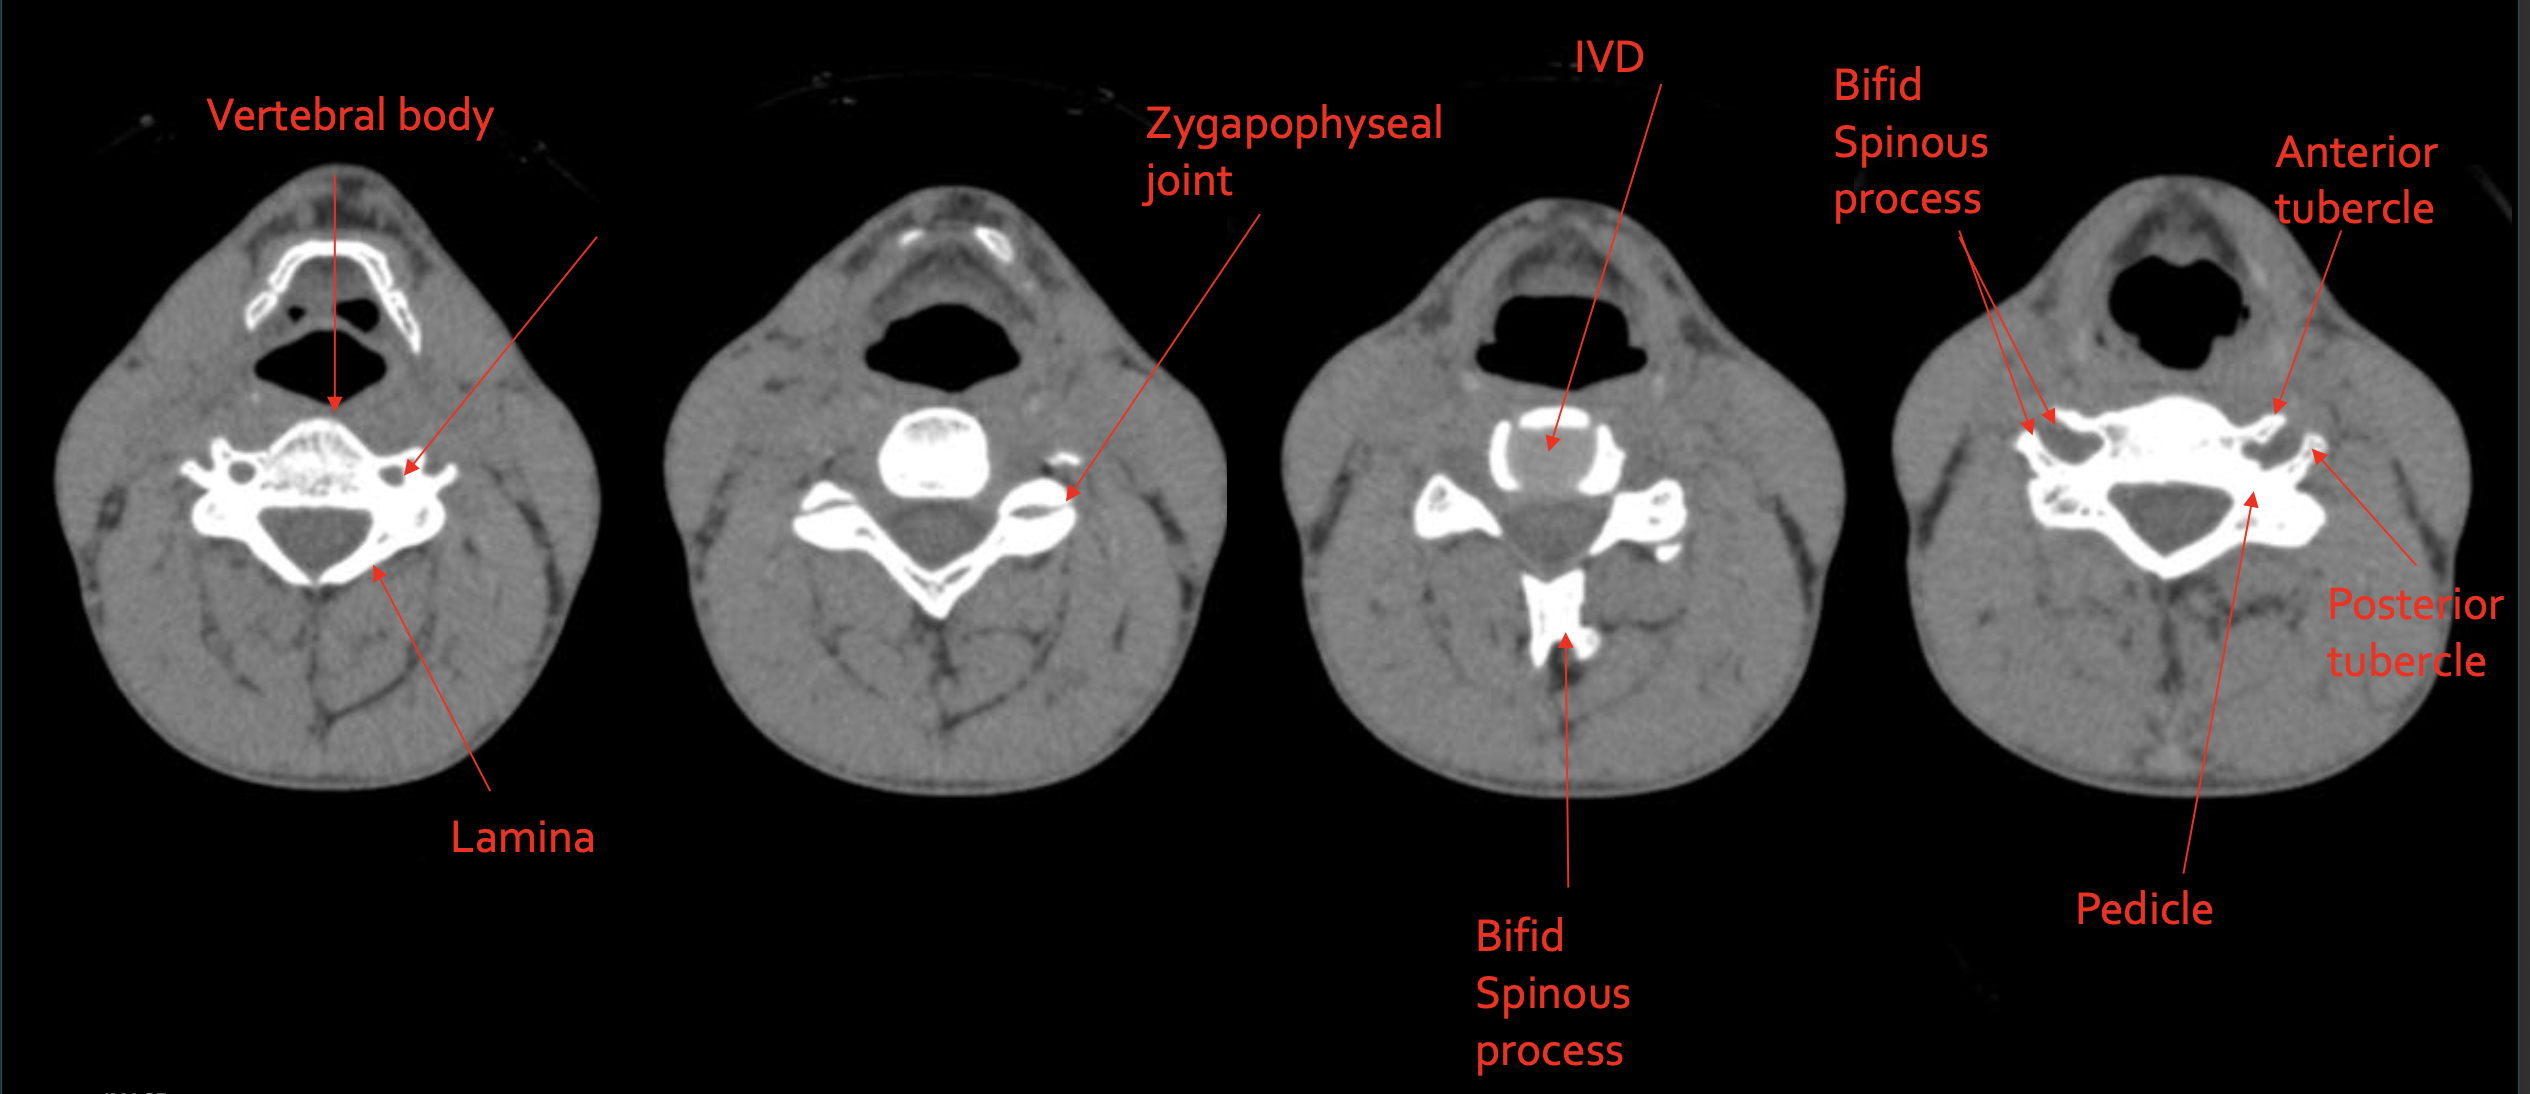

椎体

Vertebral body

椎板

Lamina

关节突关节

Zygapophyseal joint

椎间盘

IVD (Intervertebral Disc)

分叉棘突

Bifid Spinous process

前结节

Anterior tubercle

后结节

Posterior tubercle

椎弓根

Pedicle